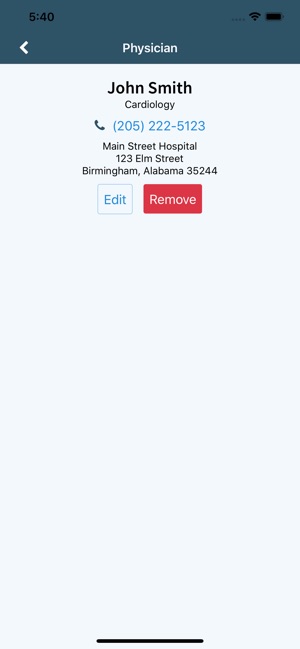

- Keep track of all your medical providers.

Our app is part of the rapidly-expanding VitalEngine network, used by medical providers worldwide. If your doctor’s office is in the VitalEngine network, it will also be able to upload documents and images to your account, so it can provide you with real-time, secure and accessible-anywhere medical information, all in a HIPAA-compliant platform.